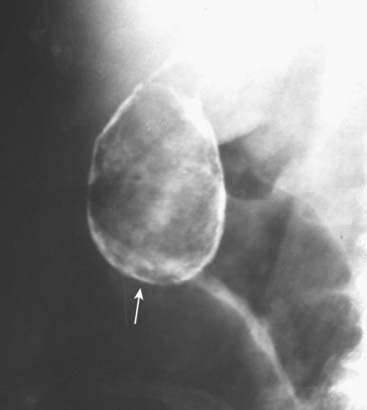

Figure 16-2 Calcified aortic aneurysm.

Calcification in the wall of the abdominal aorta is a common finding in atherosclerosis, especially in those with diabetes mellitus. In this patient, the aorta is enlarged and demonstrates a rimlike calcification (solid white arrows). The opposing wall is also calcified, but overlaps the spine. An aneurysm is present when the diameter of the abdominal aorta exceeds its normal diameter by more than 50%.